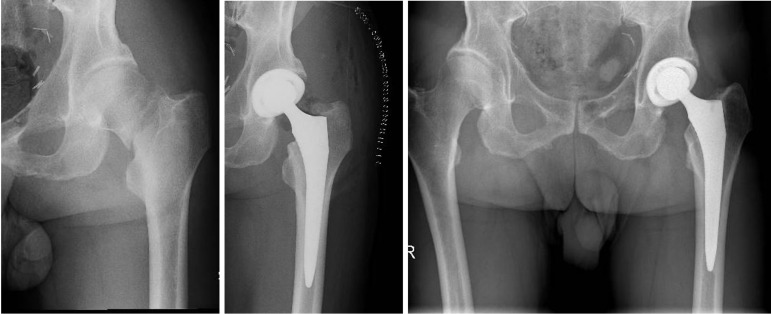

Results: The mean follow-up was 41.5 months. The Harris Hip Score (HHS) showed a mean increase of 2.74 points (mean HHS 88.52 at 6 months postoperatively and mean HHS 91.26 at the last follow-up) with statistical significance. Similarly, the Oxford Hip Score demonstrated a statistically significant difference between follow-up groups. However, the EQ5D did not show statistically significant differences among the three groups (preoperative, 6-month follow-up, and last follow-up). Revision surgery was required in 6 patients. According to Moore's criteria, 96% of the acetabular components were radiographically stable and well-integrated at the last follow-up. The Kaplan-Meier curve showed a 96% survival rate.

Conclusion: The clinical and radiographic results obtained in the short to medium term confirm the excellent performance of the Delta TT acetabular cup in terms of osseointegration, providing an optimal solution both for young patients with high functional recovery demands and for fragile patients requiring optimal stability of the acetabular component to reduce the risk of implant failure.